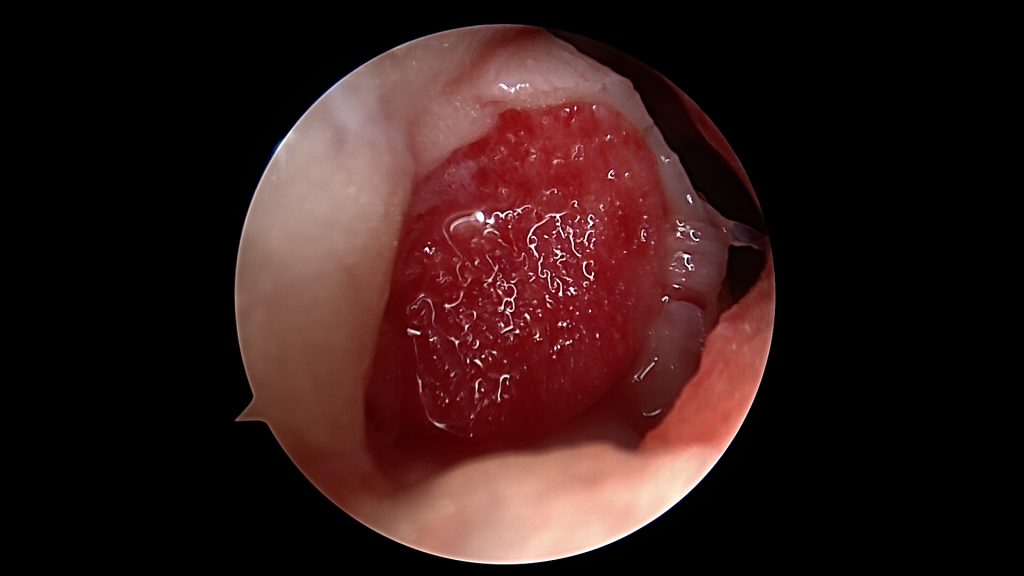

W przypadku niewielkich uszkodzeń czwartego stopnia, punktowych, poniżej 1 cm2, stosuje się odświeżenie dna ubytku. W ten sposób wydostająca się spod chrząstki krew tworzy skrzep wypełniający ubytek. Kiedy jednak jest on większy konieczne jest jego wypełnienie materiałem. Stosuje się preparaty hyaluronowe (np: Hyalofast) lub błony kolagenowe. Są one rusztowaniem dla komórek, które zagnieżdżają się w nich oraz rozpoczynają tworzenie regeneratu chrząstki stawowej.